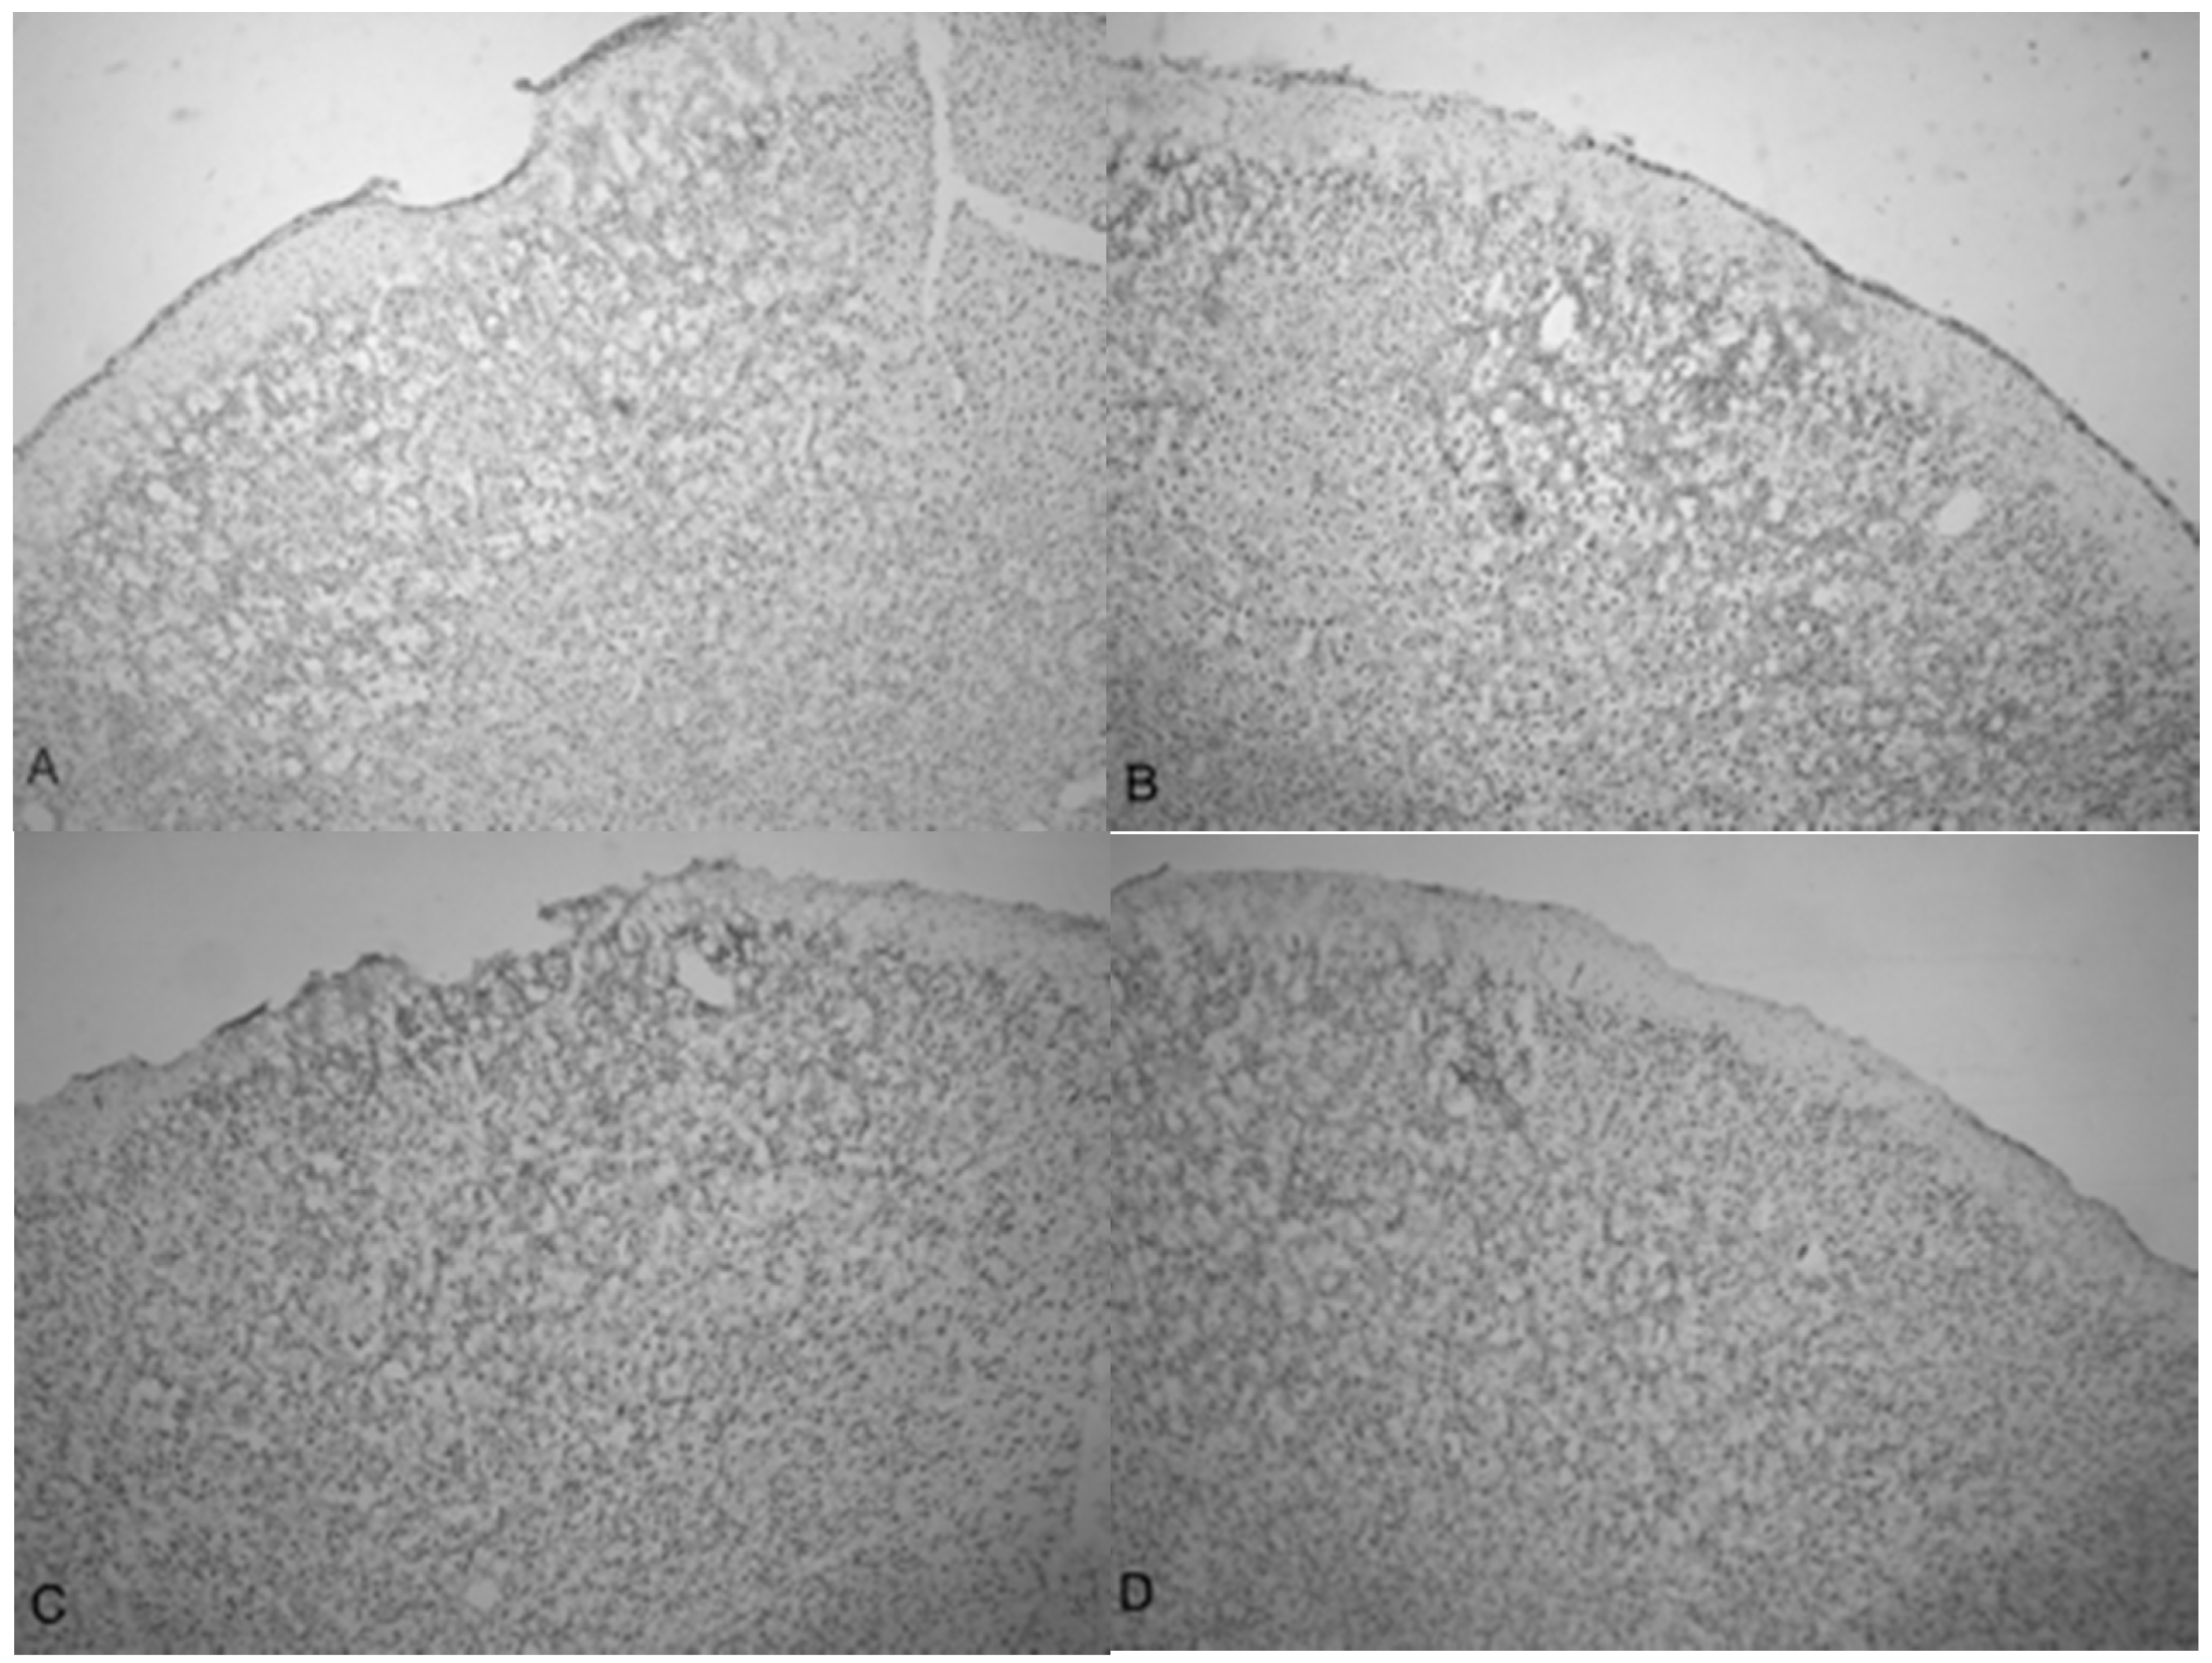

A side-by-side comparison of all four treatments is shown in Figure 6. An intact, uninjured cortex revealed no detectable damage (Figure 6A). Slight damage of the outer cortex that does not penetrate beyond the pia mater is seen in the 3.4 bar treatment (Figure 6B). The injury from the 4.2 bar treatment is much more significant than that of the 3.4 bar, penetrating beyond the pia mater and reaching cortical neurons (Figure 6C). The depth of the 4.2 bar injury can be compared to that of the 5.0 bar injury (Figure 6D). The 5.0 bar treatment is much more pervasive and penetrates even deeper into the cortex. The clearer space within the marked region (Figure 6D) clearly shows neuronal cell death.

Finally, the depth of TBI-induced injury was analyzed from the tissue slices from the 3.4, 4.2 and 5.0 bar treatment groups. The damaged cortical area from each animal was traced and outlined (see Figure 6), and a mean injured area was determined (Figure 7). The 3.4 bar treatment group had an average injury area of 1.07 mm 2. The 4.2 bar treatment group had an average injury area of 4.36   mm 2 nearly four times greater than damage caused by the 3.4 bar treatment. Finally, the 5.0 bar treatment group had an average injury area of 8.15   mm 2 which was nearly eight times greater than the 3.4 bar and nearly two times greater than the 4.2 bar injury. An ANOVA showed statistical differences among the treatment groups (F = 134.90; p < 0.001) in a dose-dependent manner.

The increasing size of the TBI is dependent on acoustic wave intensity and can be observed in Figure 6 and Figure 7, implicating the scalable nature of the Storz-D-Actor acoustic wave, produce a mild TBI (Figure 6B) or a more intense moderate TBI (Figure 6C,D). Although not part of this research, the Storz-D-Actor could conceivably produce a more severe TBI with repeated applications, resulting in much greater cell death. While disruption and fragmentation of the dura mater seemed consistent throughout the test groups, wave intensity correlated to both the size and depth of TBI (Figure 6 and Figure 7). Subsequent measurements of TBI infarct area (Figure 7) corroborate the visual evidence in the photomicrographs. TBI injury causes pyknosis, defined as when neurons condense and become darkly stained cells [33,34]. Other studies have observed similar results with dark neurons expressing apoptotic proteins Bax, BCl2 and cleaved caspase-3 [28]. Other experiments have identified the presence of jellyfish microglia that are activated after TBI insult and are part of the inflammatory process responsible for neuroprotection and reparative are cells, aiding in neuronal recovery [35].

Figure 6. Photomicrographs taken of the frontal cortex showing the overall depth of injury and due to the penetration of acoustic waves: the control (0 bar), 3.4, 4.2 and 5.0 bar TBI, respectively of Han-Wistar rats, ten days post-injury. Image (A) shows no damage from an untreated, control rat (0 bar). Image (B) shows slight damage to the outer cortex (3.4 bar). Images (C,D) show the deeper penetrating impact delivered by the 4.2 and 5.0 bar. The dotted lines show examples of the infarct boundaries traced by locating the perimeter of condensed dark cells used to calculate the expanse of the area damaged. All images were taken at 40× magnification.